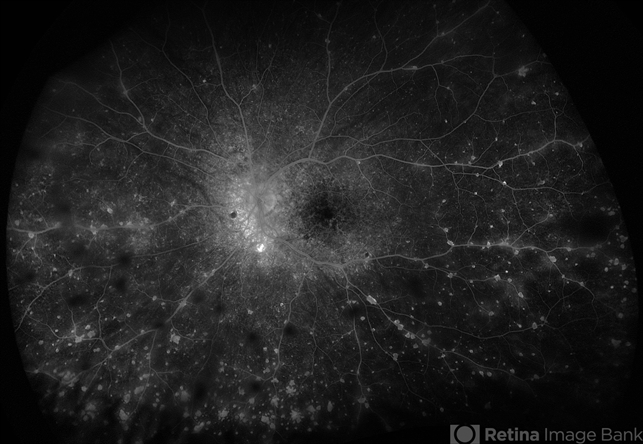

- Vogt-Koyanagi-Harada, FA, fluorescein angiogram (FA), multifocal choroiditis, panuveitis

- Fluorescein angiogram of 22 year old male with VKH syndrome. Significant cell in AC and vitreous, multiple punched-out CR scars in periphery, mild vascular leakage. Pt referred to rheumatology for immunomodulatory treatment.